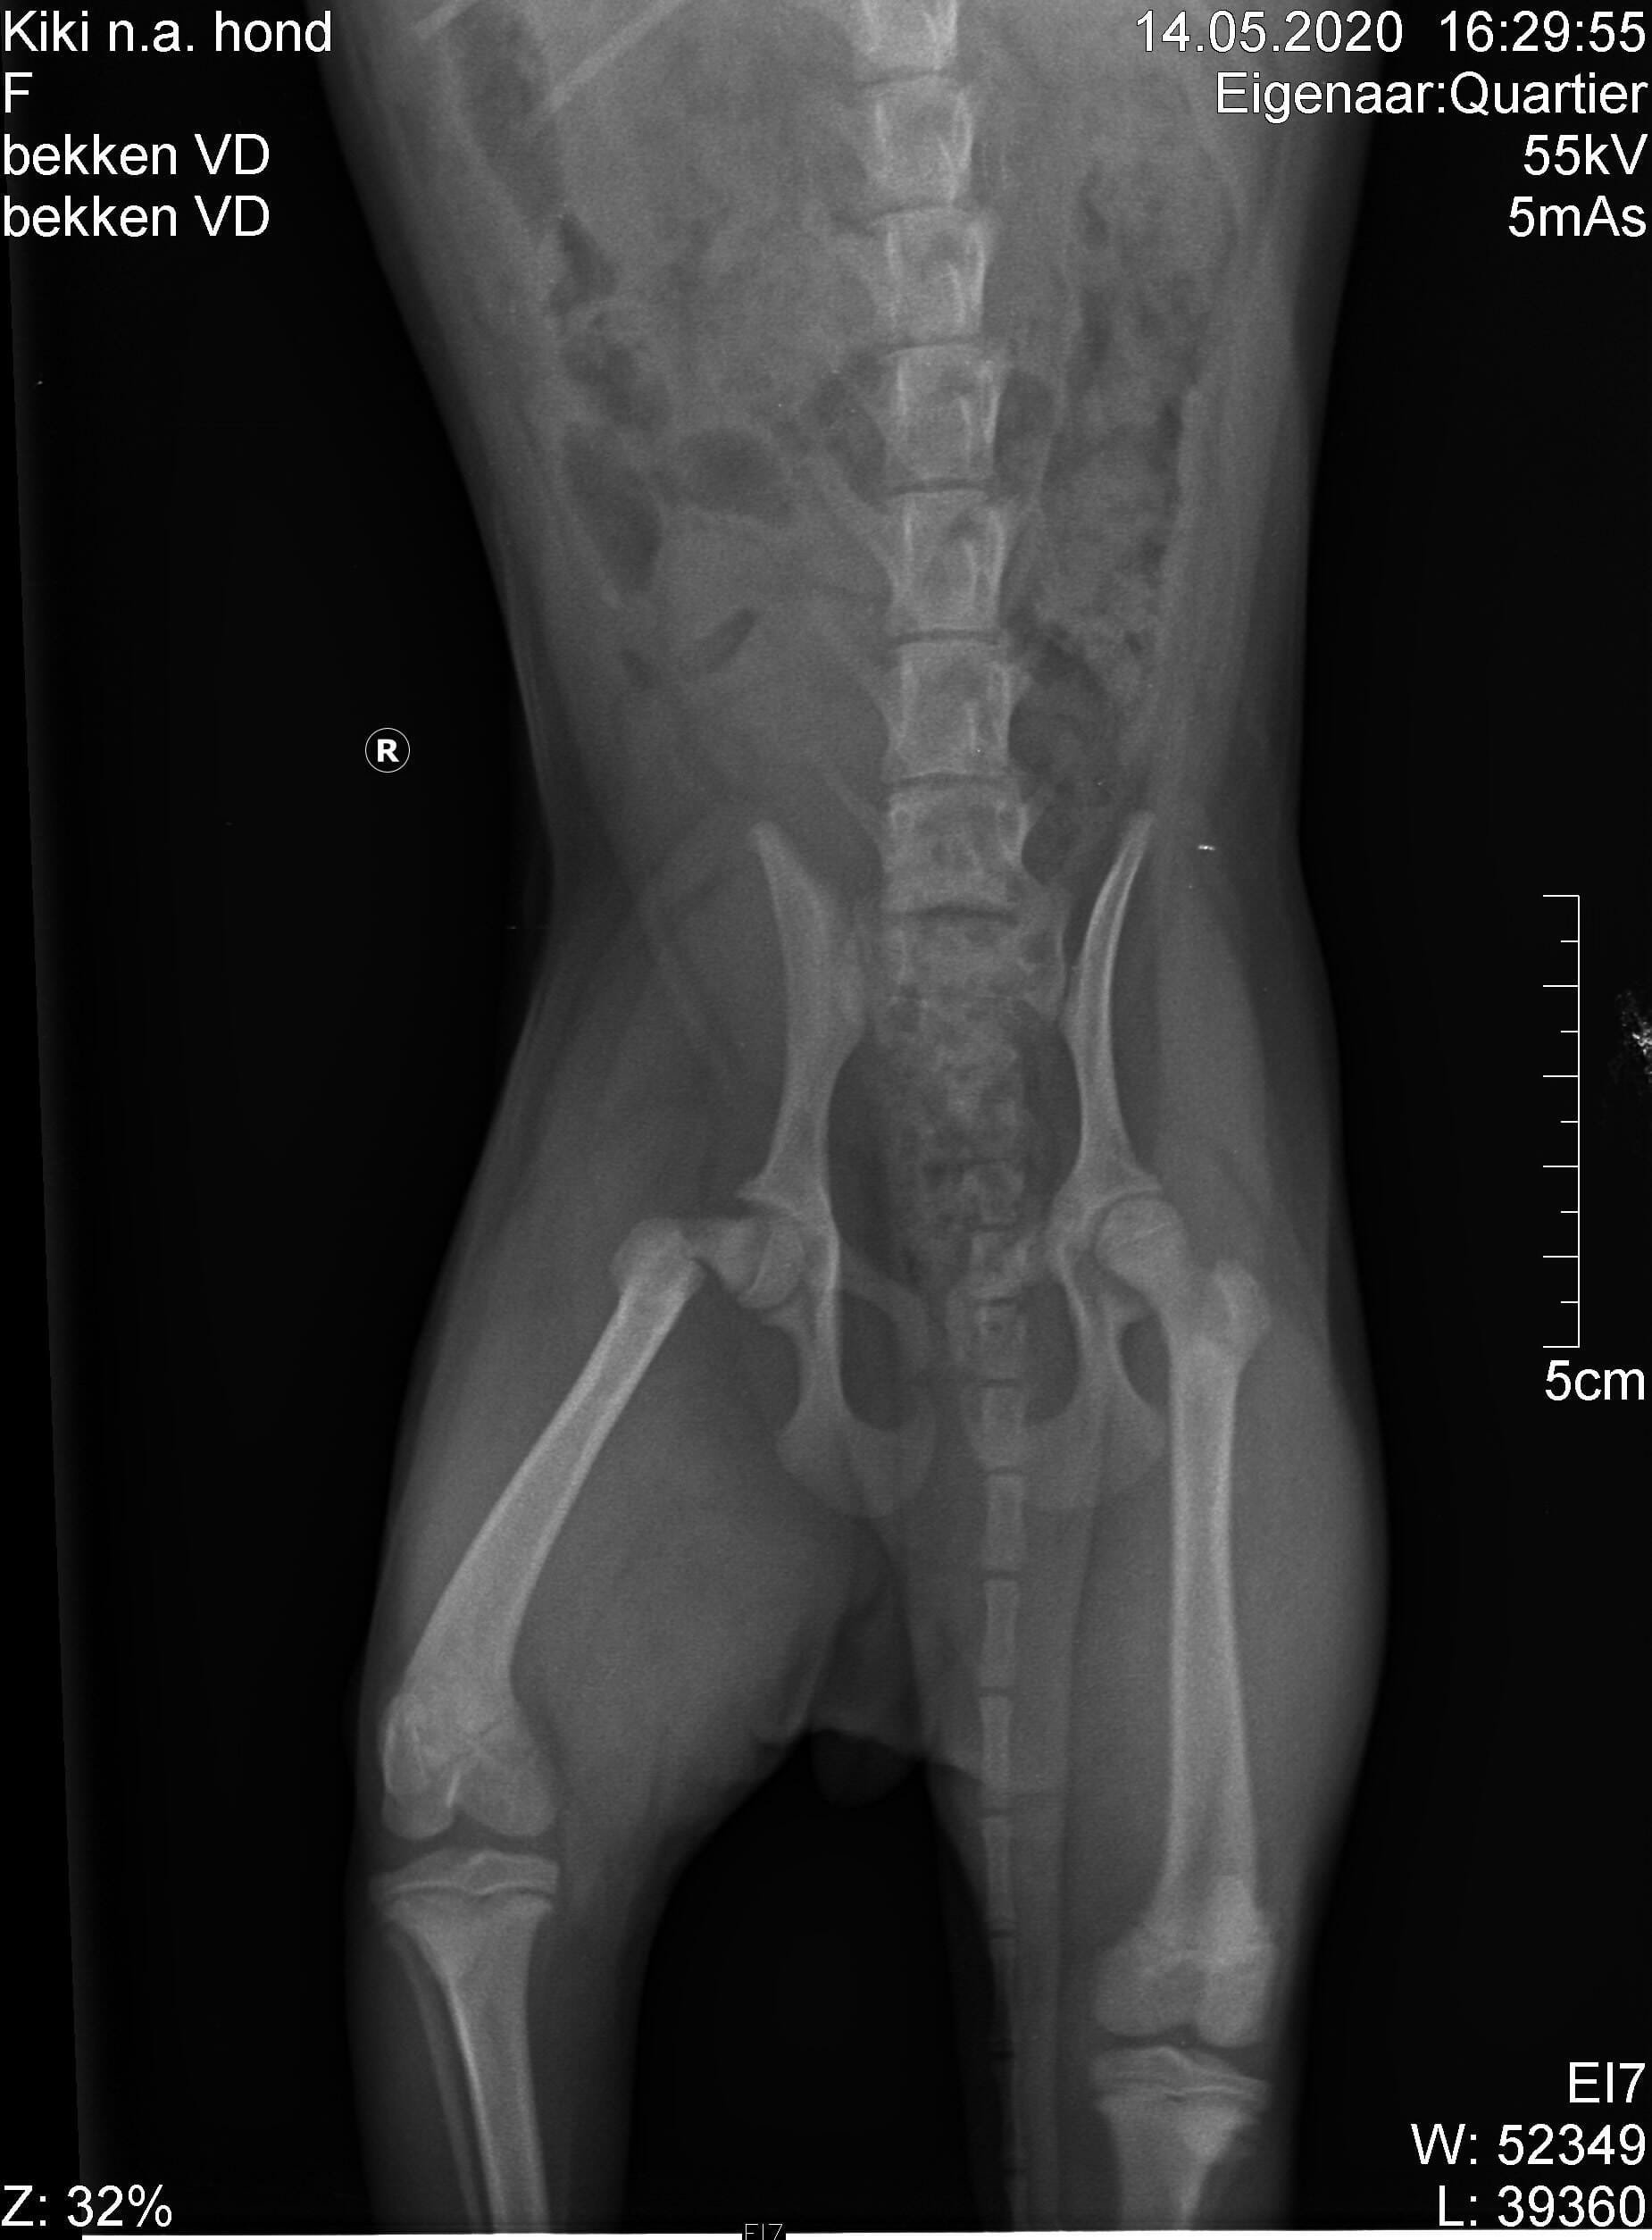

Pet's info: Dog | Mixed Breed Small (up to 22lb) | Female | unspayed | 4 months and 3 days old | 8.15 lbs

best treatment on a small dog with broken trochanter major. Vets here want to remove the top small broken piece on Monday. I want to know of that procedure is normal. They say it is very difficult to attach it again with small dogs. They told me it would be better that way and the doig will be running again in a few months.

Yes, this is a normal and common procedure for this type of injury in small dogs. The procedure of removing the femoral head (greater trochanter) is referred to as a femoral head osteotomy (FHO). I hope that Kiki has a smooth recovery!

Hello and thank you for contacting Petco Pet Education Center, formerly Petcoach. Femoral head excision is a very common surgery for fractures of the head of the femur, like this. It is relatively easy to do, and most of the dogs do very well after the surgery, If Kiki is a small breed dog, most likely she will be fine and in a few months time you will not be able to notice which leg she was operated on. Fixing a fracture of this part of femur is possible but it would involve, in my opinion placing an intramedullar pin and a plate or wire. It would be complicated but a specialist in orthopaedics should be able to do it.